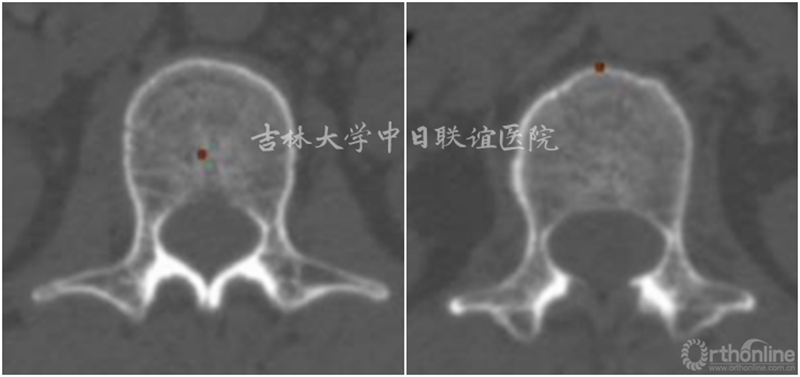

胸腰段X线/CT:未见明显异常

MRI:T1W1:相对脊髓呈等信号;T2W1:相对脊髓呈略高信号,瘤体与硬膜呈锐角,脑脊液在瘤体上缘增宽呈“杯口征”(瘤体位于硬膜下);MRI Gd:肿瘤边缘明显强化,瘤体中央伴有不均匀性增强。肿瘤与脊髓之间呈锐角,形成“肩胛征”,脊髓呈鸟嘴样改变(髓外)。

X线平片和CT检查均需要依据钙化或肿瘤引起的明显骨质改变而检出病灶,阳性率较低,但是有助于了解脊柱的稳定程度、对手术方案的制定提供帮助;脊髓造影为有创性检查,通过肿瘤与造影剂的作用(如表现为充盈缺损等)对肿瘤的定位诊断有一定的帮助,但是对于肿瘤定性存在困难。MRI对椎管内软组织分辨率高并且能够避免骨骼的伪影,根据不同肿瘤相对特征性的MRI表现可以获得较为准确可靠的定位及定性诊断,有利于术前制定合理的手术方案。

神经鞘瘤(Neurinoma)

我们回顾性分析了我院108例(111个病灶)硬膜下髓外肿瘤病例特点;神经鞘瘤69(70病灶),脊膜瘤31(31病灶),神经纤维瘤3(5病灶),畸胎瘤4(4病灶),转移性肿瘤1(1病灶)。不同肿瘤的MRI表现具有一定的特异性: